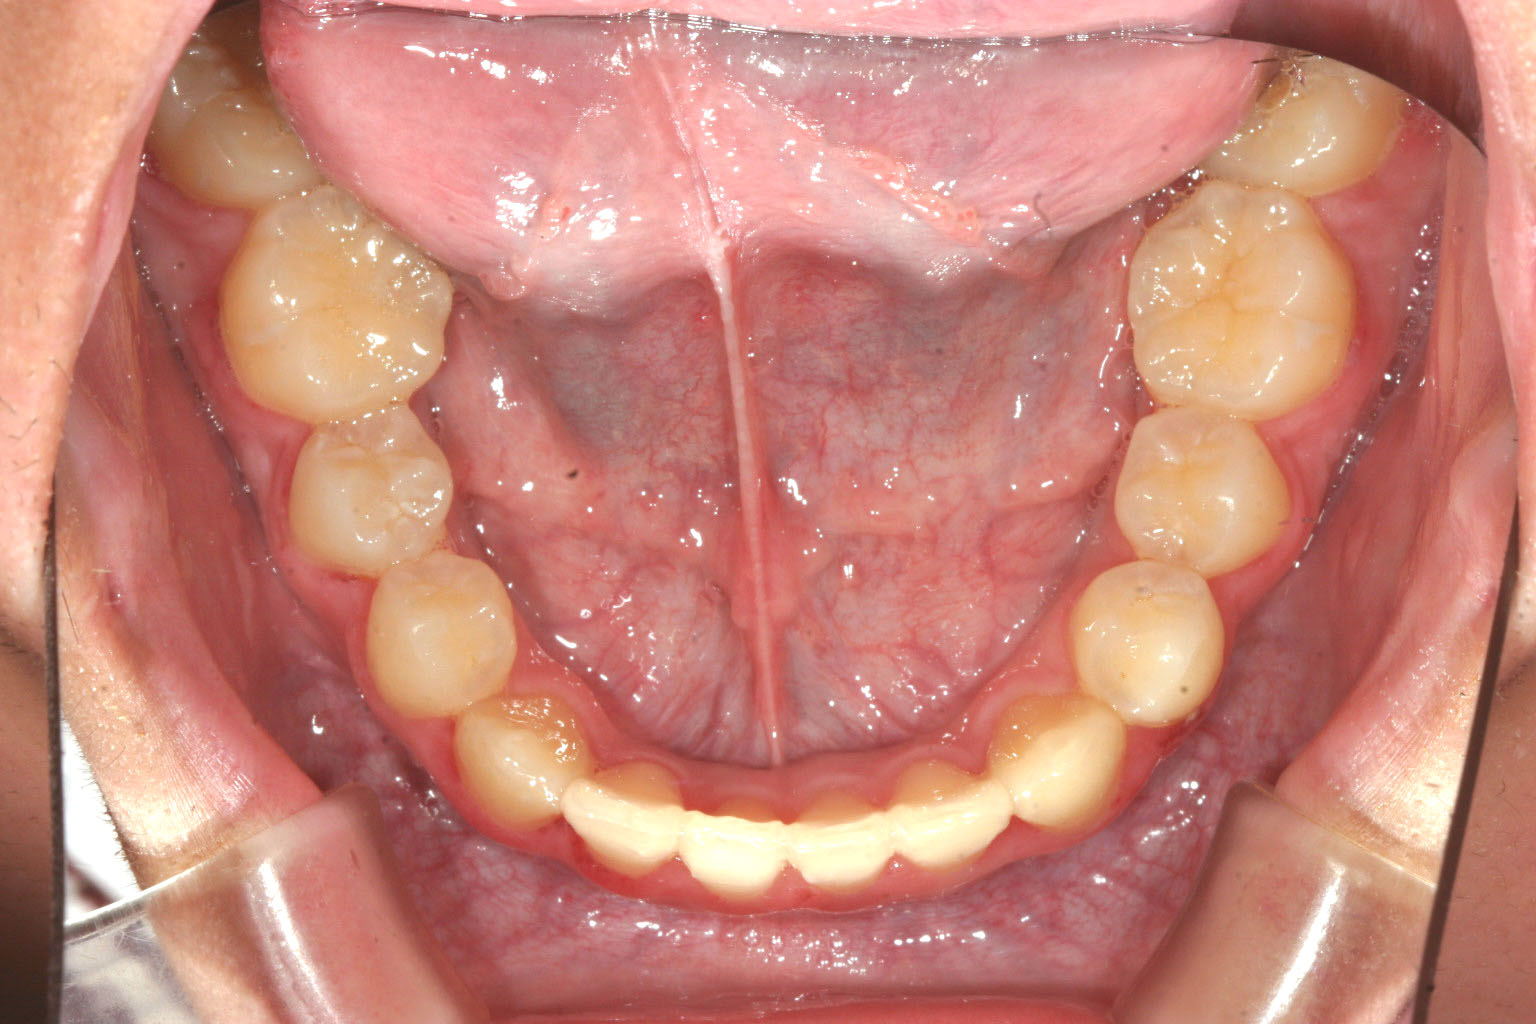

前歯が切端咬合です。

綺麗に並びました。

少し被蓋が出来受け口が改善致しました。